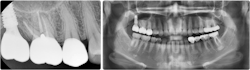

As the landscape of implantology evolves, the adoption of hydraulic lifts is poised to become the gold standard in noninvasive sinus lift surgeries, reshaping the future of dental implant procedures (figures 4–11).